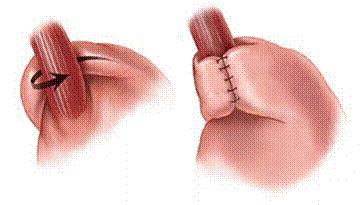

Οι χειρουργικές επεμβάσεις, λαπαροσκοπικές ή "ανοικτές" είναι ιδιαίτερα αποτελεσματικές στην αντιμετώπιση της ΓΟΠ. Η θολοπλαστική Nissen έχει δοκιμαστεί για περισσότερα από πενήντα χρόνια αντιμετωπίζοντας επιτυχώς την ΓΟΠ στο 90% των ασθενών. Κατά την επέμβαση της θολοπλαστικής ο θόλος του στομάχου, το ανώτερο τμήμα του δηλαδή, διαχωρίζεται από τους γύρω ιστούς και «τυλίγεται» γύρω από των κατώτερο οισοφάγο, αποκαθιστώντας έτσι την γαστροοισοφαγική βαλβίδα (εικ. 2). Εάν συνυπάρχει διαφραγματοκήλη γίνεται ανάταξη της μαζί με σύγκλειση των σκελών του διαφράγματος.

Εικόνα 2: Θολοπλαστική Nissen

Από τις αρχές της δεκαετίας του '90, η θολοπλαστική Nissen γίνεται λαπαροσκοπικά, και προσφέρει, από αξιόπιστα πάντα χέρια, άριστα, άμεσα και μακροπρόθεσμα αποτελέσματα. Όπως κάθε επέμβαση έτσι και η λαπαροσκοπική Nissen μπορεί να παρουσιάσει επιπλοκές όπως πόνο, προσωρινή δυσκολία στην κατάποση, στο ρέψιμο ή στον εμετό, ή σπανιότερα υποτροπή της ΓΟΠ και ανάγκη ανακατασκευής της. Παρά τις επιπλοκές που μπορεί να παρουσιάσει, η λαπαροσκοπική θολοπλαστική Nissen είναι σήμερα η πιο αποτελεσματική και δοκιμασμένη θεραπεία της ΓΟΠ με σαφή υπεροχή έναντι της φαρμακευτικής αγωγής, ιδιαίτερα στην αποφυγή μεταπλασίας Barrett.